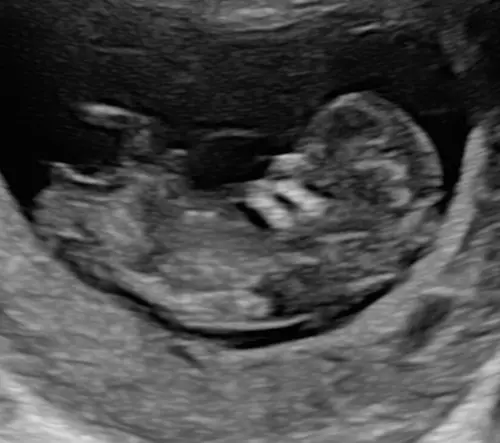

Hoi allemaal, wij hebben gisteren een prachtige termijn echo gehad met mooie beelden van ons kindje.

Alles zag er gelukkig goed uit.

Ik ben hier 11 weken en 5 dagen.

Als jullie hier een gok doen over het geslacht volgens de nub theorie? Wat denken jullie dan. 😊